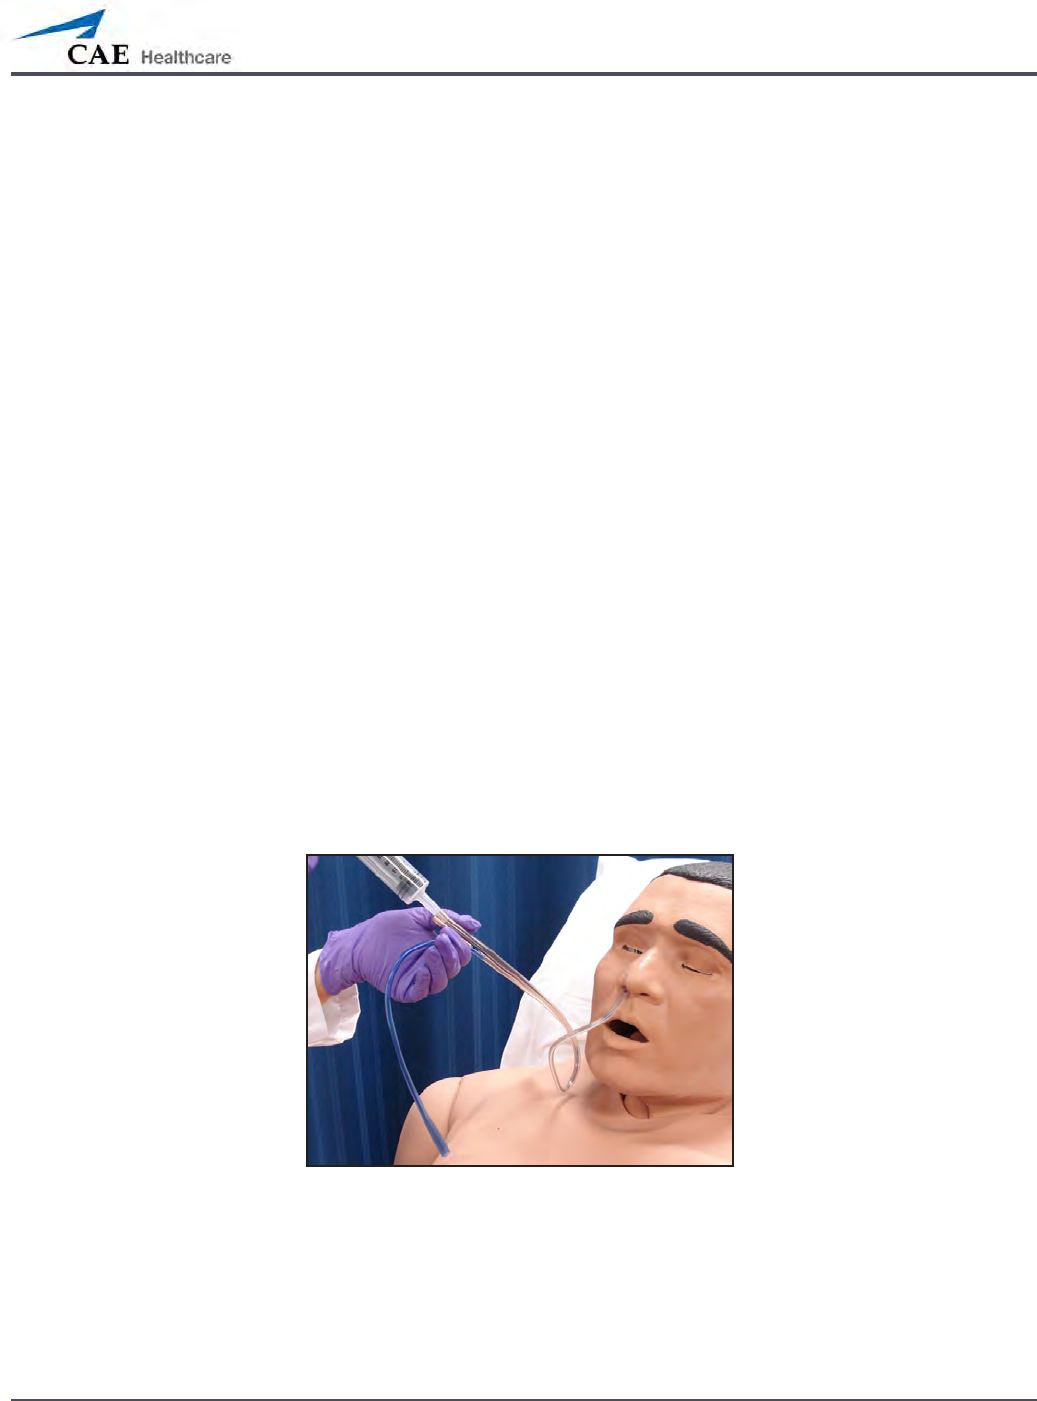

Realistic Upper Airway (Prehospital Only)

The upper airway of METIman Prehospital is designed to allow for intubation and

laryngoscopy. Oral and nasal intubation can be performed using a variety of airway devices,

including LMAs (3), endotracheal tubes (6.5 mm to 7.5 mm), nasal-pharyngeal airways (30 mm)

and oropharyngeal airways (90 mm).

Intubation

The simulator detects and responds appropriately to right mainstem intubation, and an event

is recorded in the Event Log.

Intubation incorrectly applied into the esophagus causes abdominal distension.

IMPORTANT

Airways can be damaged by improper insertion of an

airway adjunct (e.g. endotracheal tube). To protect the

airway, lubricate the adjunct prior to insertion using the

silicone spray provided.

Use ONLY the provided SILICONE SPRAY to lubricate the

adjunct. NEVER use a water-based lubricant because of

resulting residue damage.

Cricothyrotomy

Cricothyrotomy can be simulated on METIman. Before performing a needle cricothyrotomy,

the Cricothyrotomy plug must be removed, and a 2.25-inch (6-cm) length of red tape from the

roll provided must be placed over the hole.

To replicate a needle cricothyrotomy:

Spray the silicone lubricant onto the airway adjunct prior to the simulation

1.

session. To prevent damage to the simulator, always spray silicone lubricant into

the airway.

Locate the simulated cricothyroid membrane sealed with tape underneath the

2.

neck skin.

Follow standard clinical techniques and palpate to nd the cricothyroid space.

3.

Puncture the space through the neck skin of the patient simulator and into 4.

the tape “membrane.” This puncture goes all the way through to the “trachea,”

simulating the clinical procedure.

Users must replace the tape that simulates the cricothyroid membrane after each

5.

cricothyrotomy.